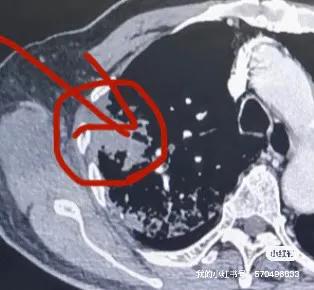

一個78歲合併冠狀動脈重度狹窄的冠心病病人,體檢發現右肺腫塊,由於不敢手術與常規穿刺活檢,在當地三甲醫院花了14800元做了血液基因檢測未發現相關驅動基因突變,準備做區域性放療,但又沒有病理診斷,最後多方打聽最終選擇一種國內特色的肺穿刺活檢技術——氬氦刀冷凍隧道式肺活檢專利技術。在局麻CT引導進行了冷凍活檢手術,活檢多條大塊組織標本,術中冰凍病理診斷是腺癌,即刻同期進行區域性完全性氬氦刀冷凍消融手術。其餘標本再次進行組織基因檢測,發現是EGFR21突變。後續直介面服奧希替尼靶向藥物治療,5個月後,腫瘤完全消失,腫大的縱隔淋巴結也恢復正常,臨床評估CR。本案例說明:1.對於不能手術、合併複雜基礎疾病或高齡的肺腫塊病人,這種特色是肺穿刺活檢技術(冷凍隧道活檢技術+穿刺標本現場冰凍病理診斷技術+同期冷凍消融技術)就是一種很好的選擇;2.對於腫瘤基因檢測,本案例顯示血液標本的準確性低於組織標本;3.對於腫瘤診療,只有精準診斷才有精準治療。